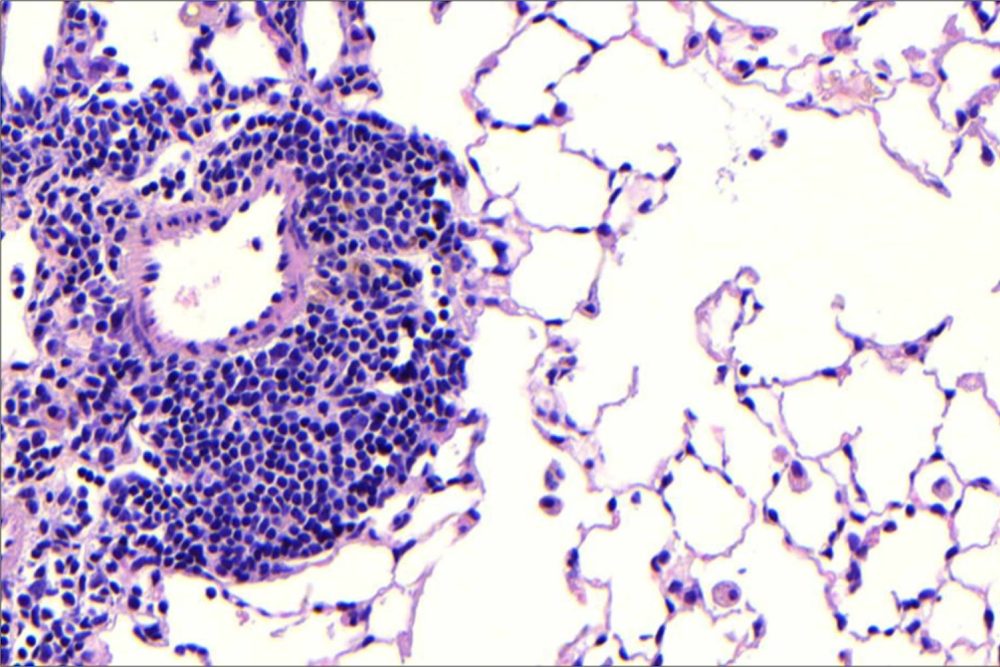

Tatsächlich gibt es viele Parallelen zwischen der Entstehung von Krankheiten in der Leber und in der Lunge. Bei COPD bilden Immunzellen neu organisierte Strukturen aus, sogenannte tertiäre Follikel. Von diesen weiß man, dass sie für das Fortschreiten der Krankheit relevant sind. Die Follikel können sich nur dann bilden, wenn der Lymphotoxin-Beta-Rezeptor in der Lunge aktiviert ist – also der gleiche Rezeptor, den Heikenwälder bereits in seiner Studie an der Leber blockiert hat. „Unser Ziel war es, herauszufinden, welche Funktion dieser Rezeptor und seine Signalwege bei der COPD einnehmen und ob wir sie für therapeutische Zwecke nutzen können“, sagt Yildirim. Die Forscherinnen und Forscher blockierten daher die Signalwege des Lymphotoxin-Beta-Rezeptors in den Lungen von Mäusen, die aufgrund chronischen Zigarettenrauchs COPD-typische Symptome entwickelt hatten (Immunzellfollikel, Fibrose und Zelltod von Lungenepithelzellen).

Das Ergebnis: Die Blockierung der Signalwege des Lymphotoxin-Beta-Rezeptors in der Lunge von COPD-Mäusen verhinderte die Formation der Immunzellfollikel. Dies wiederum unterband den Zelltod von Lungenepithelzellen. Überraschenderweise regte die Signalblockade das Lungengewebe zur selbstständigen Regeneration an. „Obwohl die Mäuse chronischem Zigarettenrauch ausgesetzt waren, konnten wir eine vollständige Wiederherstellung des Lungengewebes beobachten“, sagt Dr. Thomas M. Conlon, der in Yildirims Gruppe am Helmholtz Zentrum München forscht. „Zusätzlich sahen wir, dass mit zunehmender Heilung der Lungen auch eine Verbesserung in den Folgeerkrankungen wie Muskelschwund eintrat.“

Titelbild: Lungenabschnitt von Mäusen, die sechs Monate lang chronischem Zigarettenrauch ausgesetzt waren. Hier sind die sich entwickelnden Follikel, ein charakteristisches Merkmal der COPD, sichtbar (B-Zellen in Violett, T-Zellen in Grün und Zellkerne in Blau). Foto: Helmholtz Zentrum München